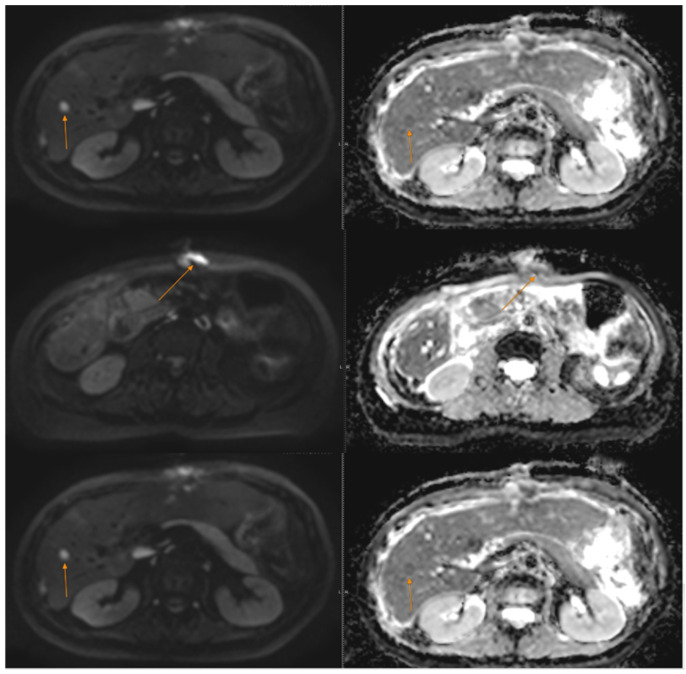

背景:胃肠道神经外胚层肿瘤(GNET),也称为胃肠道透明细胞肉瘤(CCS),是一种罕见的神经嵴源性恶性肿瘤,其特征为EWSR1-ATF1或EWSR1-CREB1融合。由于其罕见性,证据有限,没有标准管理的既定指南。GNET具有侵袭性,局部复发、转移和死亡率高。病例介绍:我们报告了一名46岁的女性,她有胃肠道癌症家族史,于2020年被诊断出患有肠道GNET。她接受了段性肠切除术作为多模式治疗的第一步。经过三年的随访,她出现了肝脏和腹膜转移。2023年11月,她开始联合使用抗vegf酪氨酸激酶抑制剂cabozantinib和免疫检查点抑制剂nivolumab。患者病情稳定18个月,耐受性良好,无不良事件发生。肿瘤的分子分析显示EWSR1-CREB1融合,支持选择靶向治疗和免疫治疗作为首选治疗方法。结论:免疫治疗和靶向治疗显示出GNET/CCS治疗的前景,但缺乏临床标准,证据主要来自病例报告。需要更多的数据来确定这种非常罕见疾病的最佳治疗顺序和组合。

Background: Gastrointestinal neuroectodermal tumour (GNET), also known as clear cell sarcoma (CCS) of the gastrointestinal tract, is a rare neural crest-derived malignancy characterized by EWSR1-ATF1 or EWSR1-CREB1 fusions. Due to its rarity, there is limited evidence and no established guidelines for standard management. GNET is aggressive, with high rates of local recurrence, metastasis, and mortality. Case Presentation: We report the case of a 46-year-old woman with a family history of gastrointestinal cancers who was diagnosed in 2020 with an intestinal GNET. She underwent a segmental enterectomy as the first step of multimodal therapy. After three years of follow-up, she developed hepatic and peritoneal metastases. In November 2023, she began combined therapy with the anti-VEGF tyrosine kinase inhibitor cabozantinib and the immune checkpoint inhibitor nivolumab. The patient has maintained stable disease for 18 months with good tolerance and no adverse events. Molecular analysis of the tumour, which showed an EWSR1-CREB1 fusion, supported the selection of targeted therapy and immunotherapy as the preferred treatment approach. Conclusions: Immunotherapy and targeted therapy show promise for GNET/CCS treatment, but clinical standards are lacking, and evidence comes primarily from case reports. Additional data are needed to determine the best sequence and combination of therapies for this very rare disease.